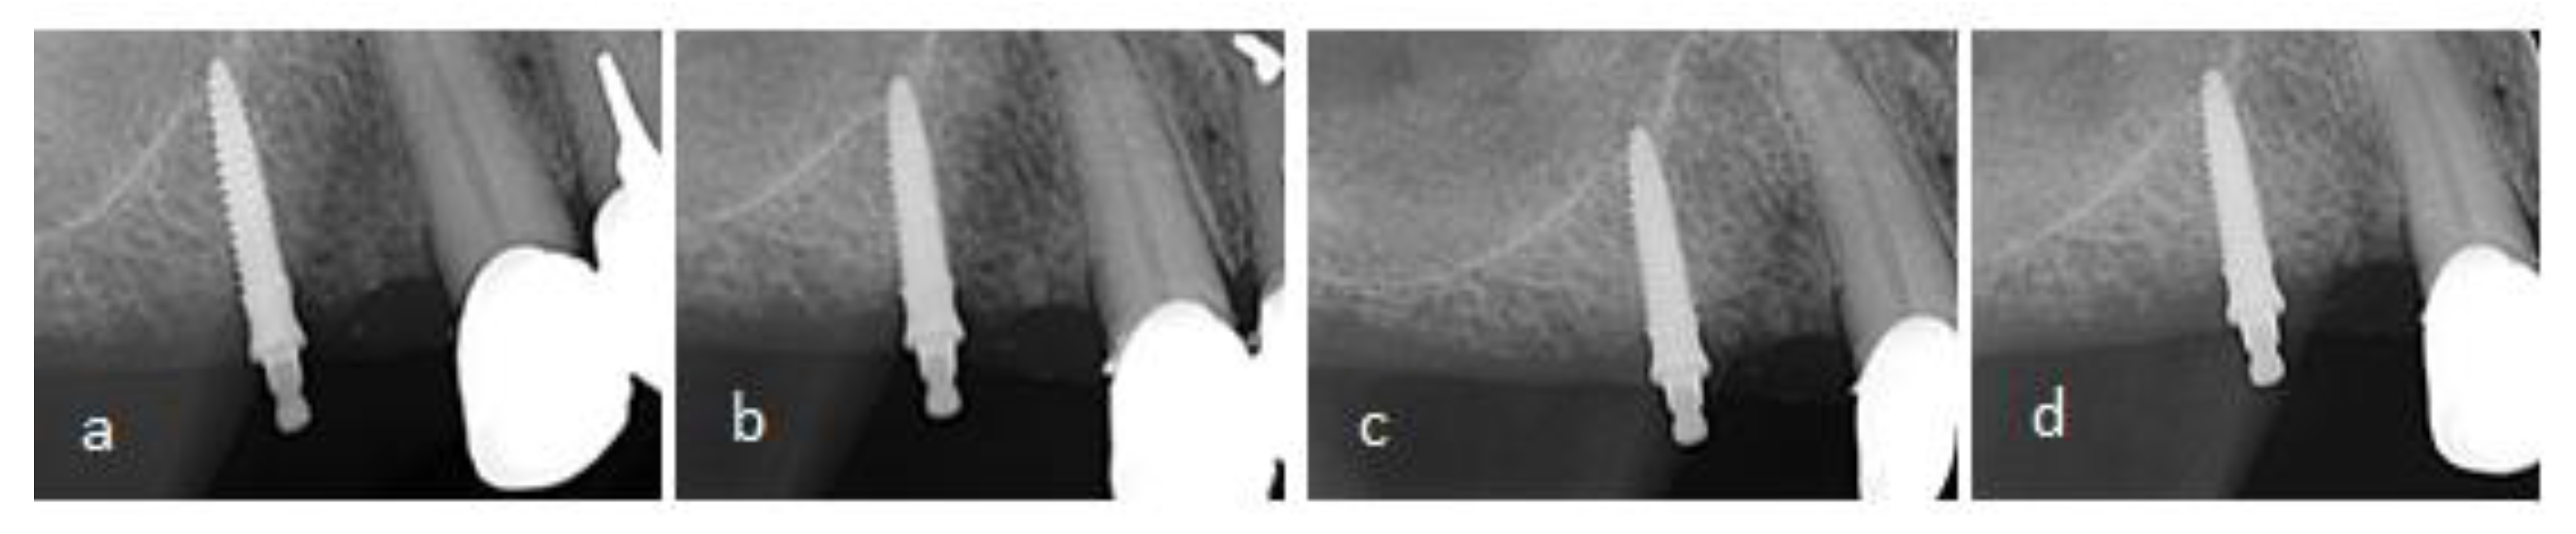

2.5. Clinical and Radiographic Evaluation